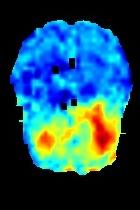

Current unsupervised anomaly localization approaches rely on generative models to learn the distribution of normal images, which is later used to identify potential anomalous regions derived from errors on the reconstructed images. However, a main limitation of nearly all prior literature is the need of employing anomalous images to set a class-specific threshold to locate the anomalies. This limits their usability in realistic scenarios, where only normal data is typically accessible. Despite this major drawback, only a handful of works have addressed this limitation, by integrating supervision on attention maps during training. In this work, we propose a novel formulation that does not require accessing images with abnormalities to define the threshold. Furthermore, and in contrast to very recent work, the proposed constraint is formulated in a more principled manner, leveraging well-known knowledge in constrained optimization. In particular, the equality constraint on the attention maps in prior work is replaced by an inequality constraint, which allows more flexibility. In addition, to address the limitations of penalty-based functions we employ an extension of the popular log-barrier methods to handle the constraint. Comprehensive experiments on the popular BRATS'19 dataset demonstrate that the proposed approach substantially outperforms relevant literature, establishing new state-of-the-art results for unsupervised lesion segmentation.